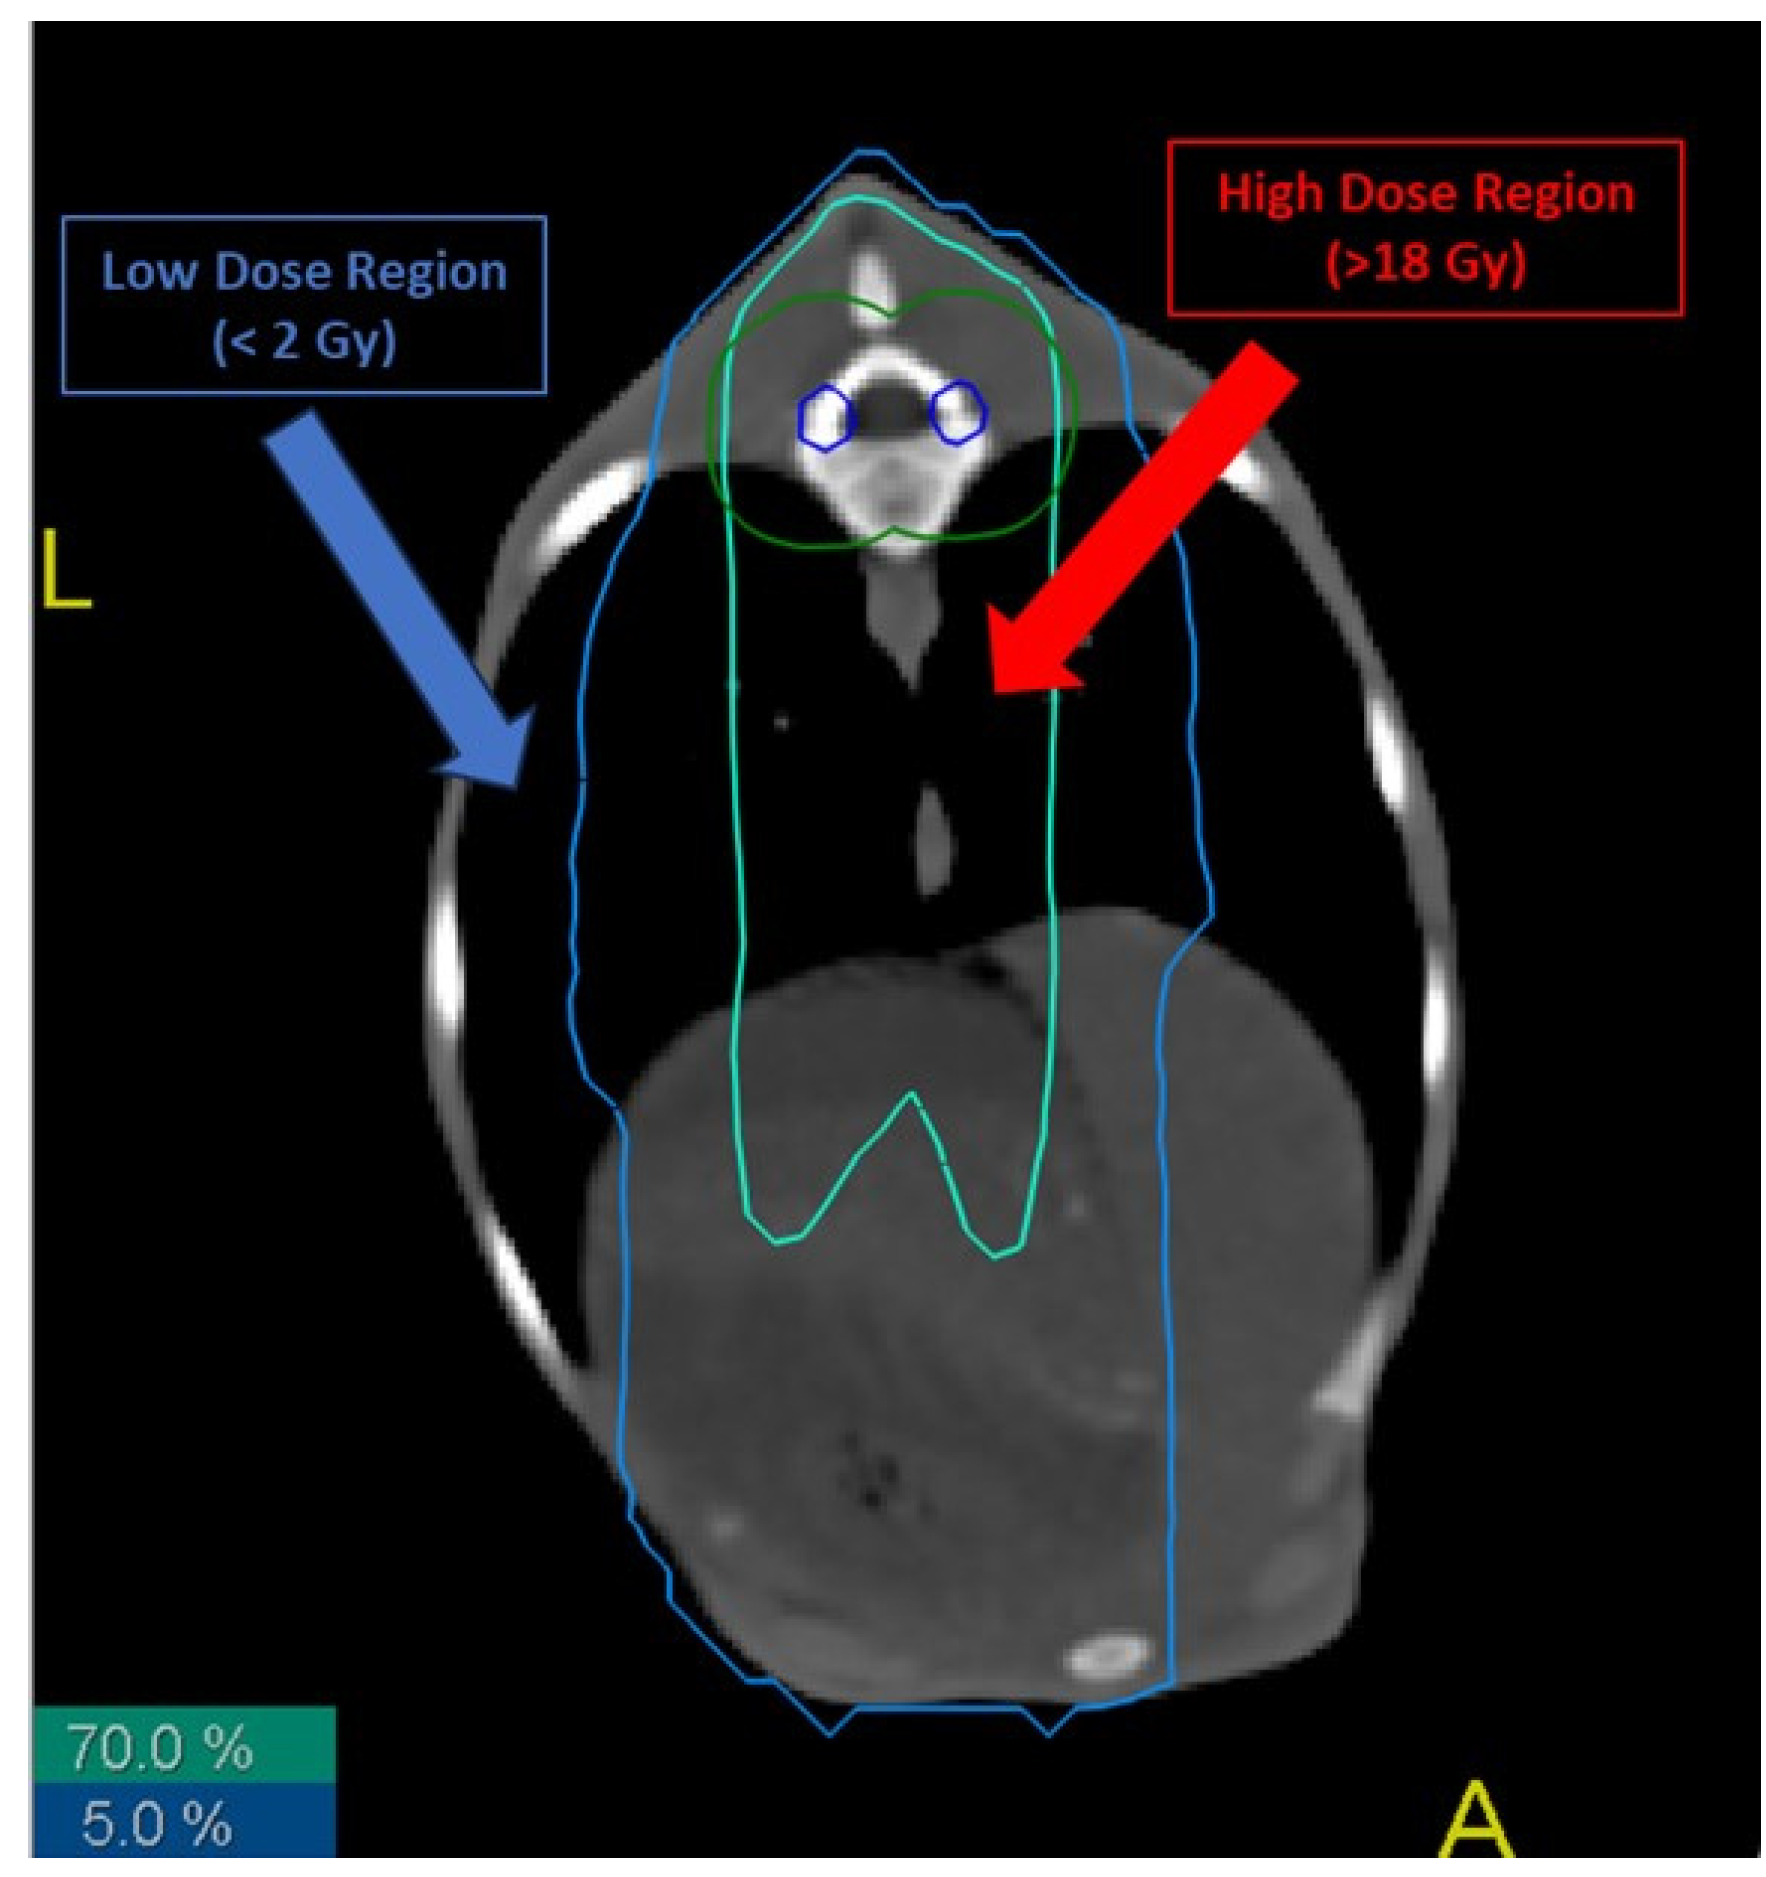

- Low-dose (LD) region: area of the sheep that received a total dose lower than 2 Gy.

- High-dose (HD) region: area of the sheep that received a total dose higher than 70% of the total dose to the thecal sac, i.e., more than 18 Gy.